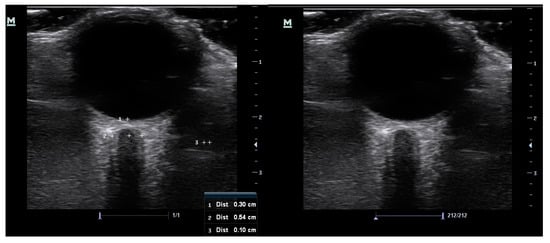

3.2. ONSD Measurements

| Variable (mm) | Mean | SD | 95% CI | Minimum | Maximum |

|---|---|---|---|---|---|

| ONSD 1 | 5.0 | 0.34 | 5.0–5.1 | 4.3 | 5.8 |

| ONSD 2 | 5.1 | 0.34 | 5.0–5.1 | 4.3 | 6.0 |

| Mean ONSD | 5.1 | 0.33 | 5.0–5.2 | 4.4 | 5.9 |